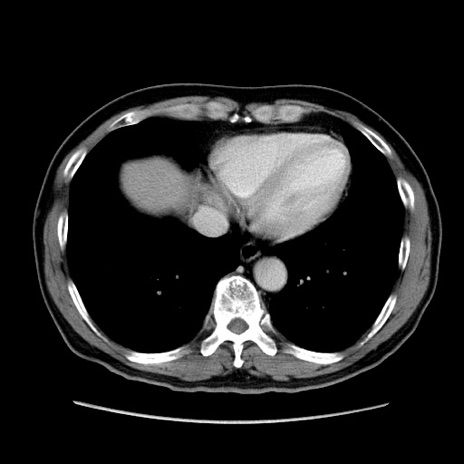

症例34(横断像)

【症例】60歳代 男性

【主訴】右鼠径部膨隆

【現病歴】1年程前より右鼠径部膨隆あり。自己にて還納可能だったため放置していた。3時間前より右鼠径部の脱出を認め、還納困難となり受診。

【身体所見】右鼠径部に小児頭大の膨隆あり。弾性硬であり、用手還納は困難。左鼠径部にも膨隆を認める。脱出はなし。